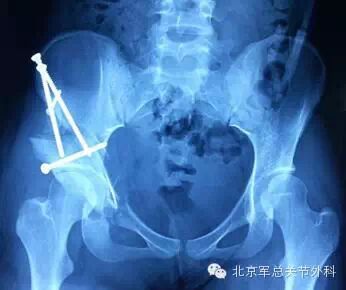

术后X线显示右髋臼顶倾斜角恢复为5.5°,外CE29°。右侧髋臼负重关节面和股骨头覆盖基本恢复正常,有利于关节的长期生存。